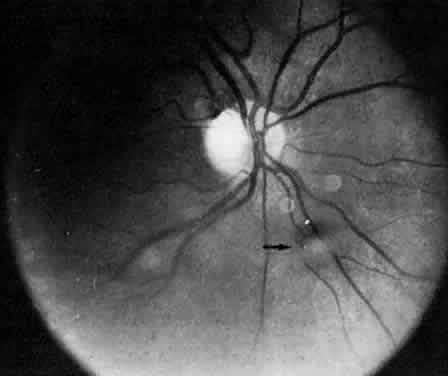

Retinal changes that can occur in pars planitis include perivascular sheathing of the retinal venules (periphlebitis), cystoid macular edema, and optic disc edema (Figs. 3 and 4). In cases of chronic cystoid macular edema, epiretinal membrane formation often occurs.4,13,27

Fig. 3. Pars planitis. Cystoid macular edema. Black arrows point to a halo of edema surrounding the macula. Open arrows point to cysts in the macula.

Fig. 4. Pars planitis. Fluorescein angiogram showing a petaloid staining pattern in the macula.